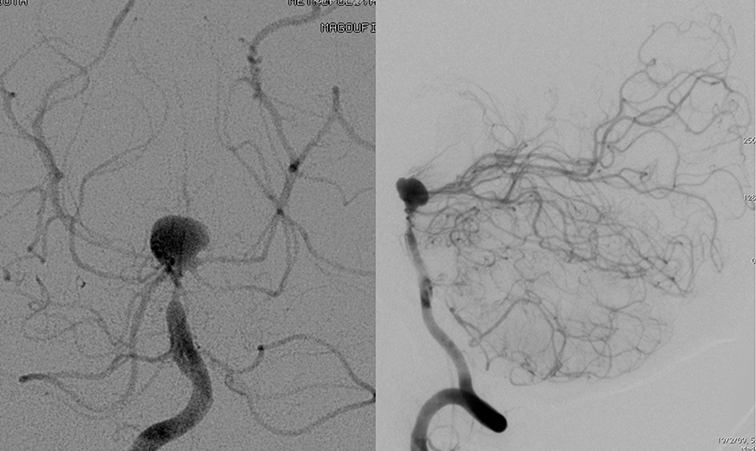

Εμβολισμός ανευρυσμάτων εγκεφάλου ευρέως αυχένος με Stent (Stent Assisted - Coiling)

Tά αποτελέσματα του εμβολισμού με coils, εξαρτώνται αποκλειστικά από τη γεωμετρία του ανευρύσματος. H ευρύτητα του αυχένα, μπορεί να οδηγήσει σε θρομβοεμβολικές επιπλοκές (λόγω της πρόπτωσης των σπειραμάτων στο θυγατρικό αγγείο) και σε επανασηραγγοποίηση του ανευρύσματος (λόγω της σύμπτωσης των σπειραμάτων). Παρά το ότι ο εμβολισμός με μπαλόνι προστασίας είναι τεχνικά εφικτός η διατήρηση του αποτελέσματος σε fololw-up δεν είναι ικανοποιητική, με υψηλά ποσοστά επανασηραγγοποίησης σε αυτή την κατηγορία ανευρσμάτων με ευρύ αυχένα.

Γιά να ξεπεραστεί αυτό το πρόβλημα, τοποθετούμε ειδικά αυτο-εκπτυσσόμενα stents μπροστά από τον ευρύ αυχένα του ανευρύσματος, ώστε να εμποδιστεί η πρόπτωση των coils εντός του θυγατρικού αγγείου. Tά σπειράματα εισάγονται στην κοιλότητα του ανευρύσματος διά μέσου των μικροπόρων του stent.

H τοποθέτηση του stent κατά μήκος του αυχένα του ανευρύσματος είναι τεχνική κατάλληλη γιά ανευρύσματα που εκφύονται από το πλάγιο τοίχωμα της έσω καρωτίδος, της σπονδυλικής και της βασικής αρτηρίας, ακόμη και παρά την έκφυση κλάδων όπως η οφθαλμική, η οπίσθια αναστομωτική, η πρόσθια χοριοειδής, η PICA ή AICA.

Σε ανευρύσματα διχασμών όπως της βασικής αρτηρίας, του διχασμού της έσω καρωτίδος ή της μέσης εγκεφαλικής και της πρόσθιας αναστομωτικής αρτηρίας, μπορούμε να χρησιμοποιήσουμε ακόμα και δύο stents (διαμόρφωση T-stenting, Y-stenting, X-stenting) ώστε να καλυφθεί πλήρως όλος ο αυχένας.

Τα stents εκτός από την τεχνική δυνατότητα εμβολισμού ευρέως αυχένος ανευρυσμάτων, τροποποιούν την ροή μπροστά στον αυχένα του ανευρύσματος (flow diversion) και προάγουν την ενδο-ανευρυσματική θρόμβωση και τελικά την ενδοθηλιοποίηση στο επίπεδο του αυχένα, άρα την οριστική ίαση.

Πρόσφατη εξέλιξη μετά τα laser-cut stents με ανοικτά κελιά (open-cells), είναι τα braided-stents από νιτινόλη, που έχουν πολύ μικρό προφίλ και καλύτερη πρόσφυση στην αγγειακή ανατομία σε θέσεις αγγειακών καμπών.

Έχουν κλειστά κελιά (closed-cells), πυκνότερη κάλυψη από μέταλλο και προκαλούν αποτελεσματικότερη ελάττωση της εισροής που διευκολύνει την ενδοανευρυσματική θρόμβωση, με καλύτερα αποτελέσματα σε σύγκριση με τα open-cell laser-cut stents. Επιπλέον είναι στο 90% επανακτήσιμα και επανατοποθετήσιμα (re-sheathable). Το μεγαλύτερο πλεονέκτημά τους όμως είναι ότι μπορούν να τοποθετηθούν με τα νέα μπαλόνια διπλού αυλού (double lumen balloons). Με αυτό τον τρόπο πρώτα μπορούμε να εμβολίσουμε το ανεύρυσμα με την τεχνική με μπαλόνι και να επιτύχουμε καλή πυκνότητα πλήρωσης χρησιμοποιώντας μπαλόνι διπλού αυλού και στην συνέχεια με τον ίδιο καθετήρα του μπαλονιού να τοποθετήσουμε το braided stent μπροστά από τον αυχένα του ανευρύσματος.